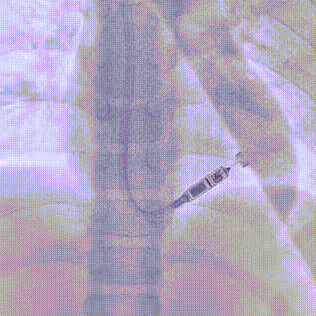

手术在全麻下进行,在超声引导下成功穿刺右侧颈内静脉,置入8F鞘管并提前置入Proglide血管缝合器。经鞘管送入导丝,稳定通路后,将Micra AV递送系统沿导丝轻柔推进,经上腔静脉、右心房进入右心室。术中采用多角度X线透视(LAO 30°、RAO 30°)及心腔内超声(ICE)辅助,精确引导递送系统定位至右室间隔中位。

提前置入 Proglide 血管缝合器